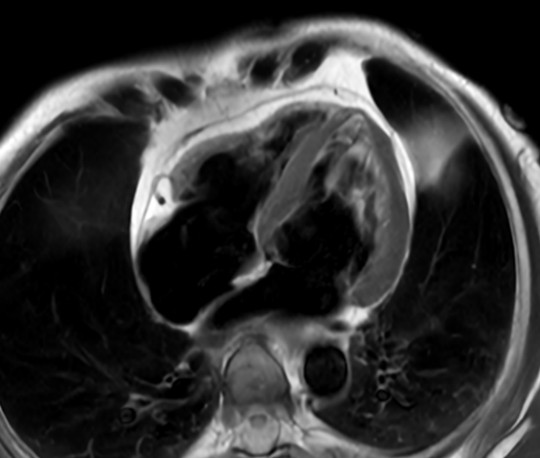

Comprehensive Cardiac with SmartSpeed Precise